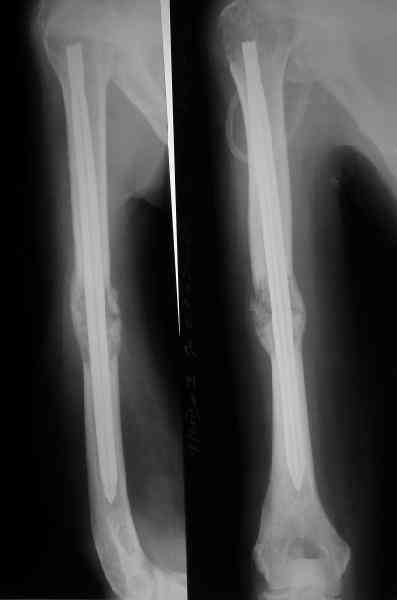

Женщина 53 лет получила патологический перелом правого плеча в феварле, и левого в марте - mts из невыясненного первичного очага.

Онкологи провели облучение, руки на косынки, время от времени наблюдают, вводили зомету.На нас вышли родственники. Состояние пациентки уже не очень, анемия (Hb -50-60 г/л), исхудалв, но асцита нет, в легких чисто. Поскольку женщина совершенно беспомощна, решили сделать остеосиннтез.

Сегодня сделали, Fixion диаметром 7,4 мм. Обе пперации продолжались по 7 мин. Картинки в приложении. Наркоз был диприваном, на спонтанном дыхании. По крайней мере, пока довольны хотя бы анестезиологи, похоже, не верили, что управимся меньше, чем за час ;-)

Гвоздик 7,4 расширяется до 11 мм. Не маловато ли, судя по снимкам?

Обсалютным показанием для использования этого стержня,из моей практики, являетются поперечные переломы диафиза пдечевой и большеберцовой костей.Преимущество его в удобстве репозиции и продалжительности операчии.Недостаток в сдабой ротационной стабильности.Учитывая состояние больной,метод был выбран правильно.Мы этих больных оперируем тогда когда приблизительный срок выживания превышает шесть месяцев и конечно же всотрудничестве с окологами.

7,4 мм, рсширяющийся до 11 мм, в принципе, достаточно для плеча. Хотя мне тоже показалось, что можно было бы и потолще. Вообще есть и следующий диаметр, 8,5 мм, расширяющийся до 13,5 мм, но его в наличии на сегодня не было.